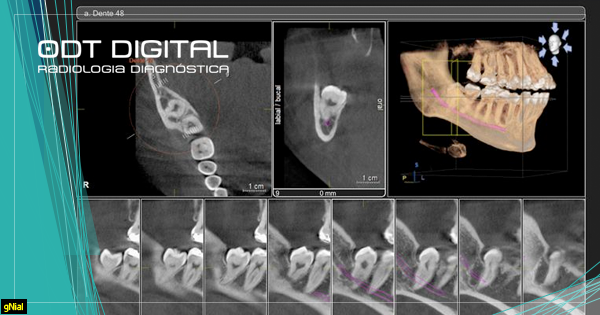

A Tomografia Computadorizada é uma técnica radiográfica que consiste na aquisição volumétrica de imagens de tecidos duros e moles. Esta